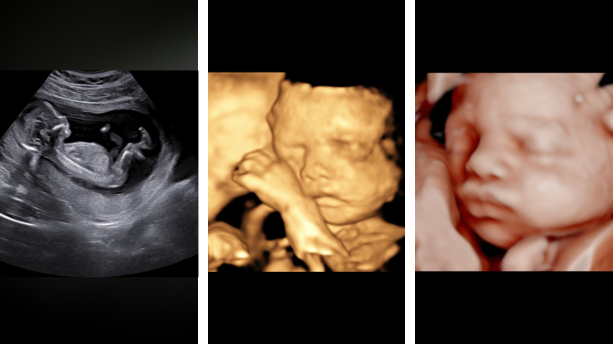

Discover our complete range of ultrasound services for pregnant women, designed with the highest precision and attention to detail to accompany you during this special stage.